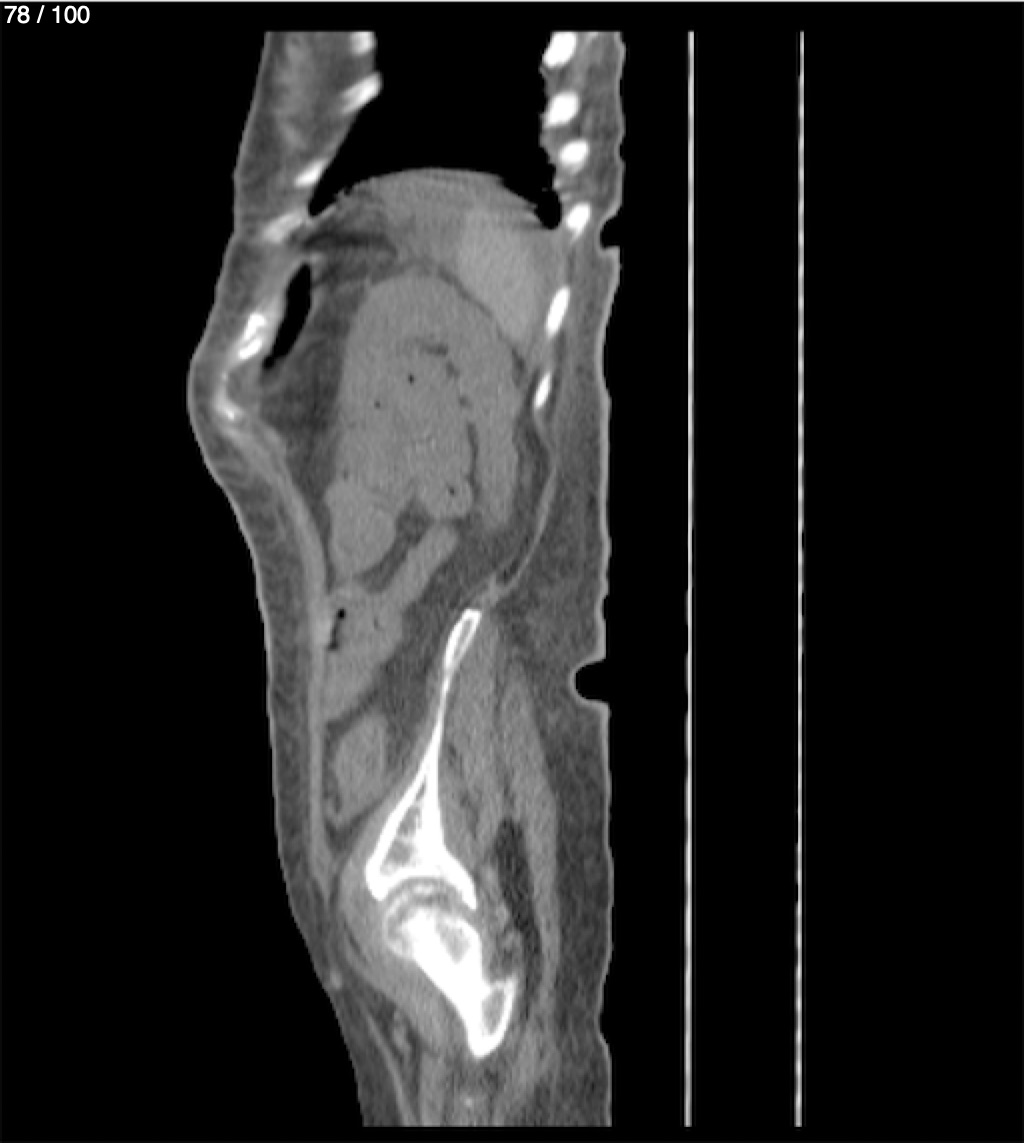

Hilda Geronimo Mendez 60A - T.C Abdomen Simple